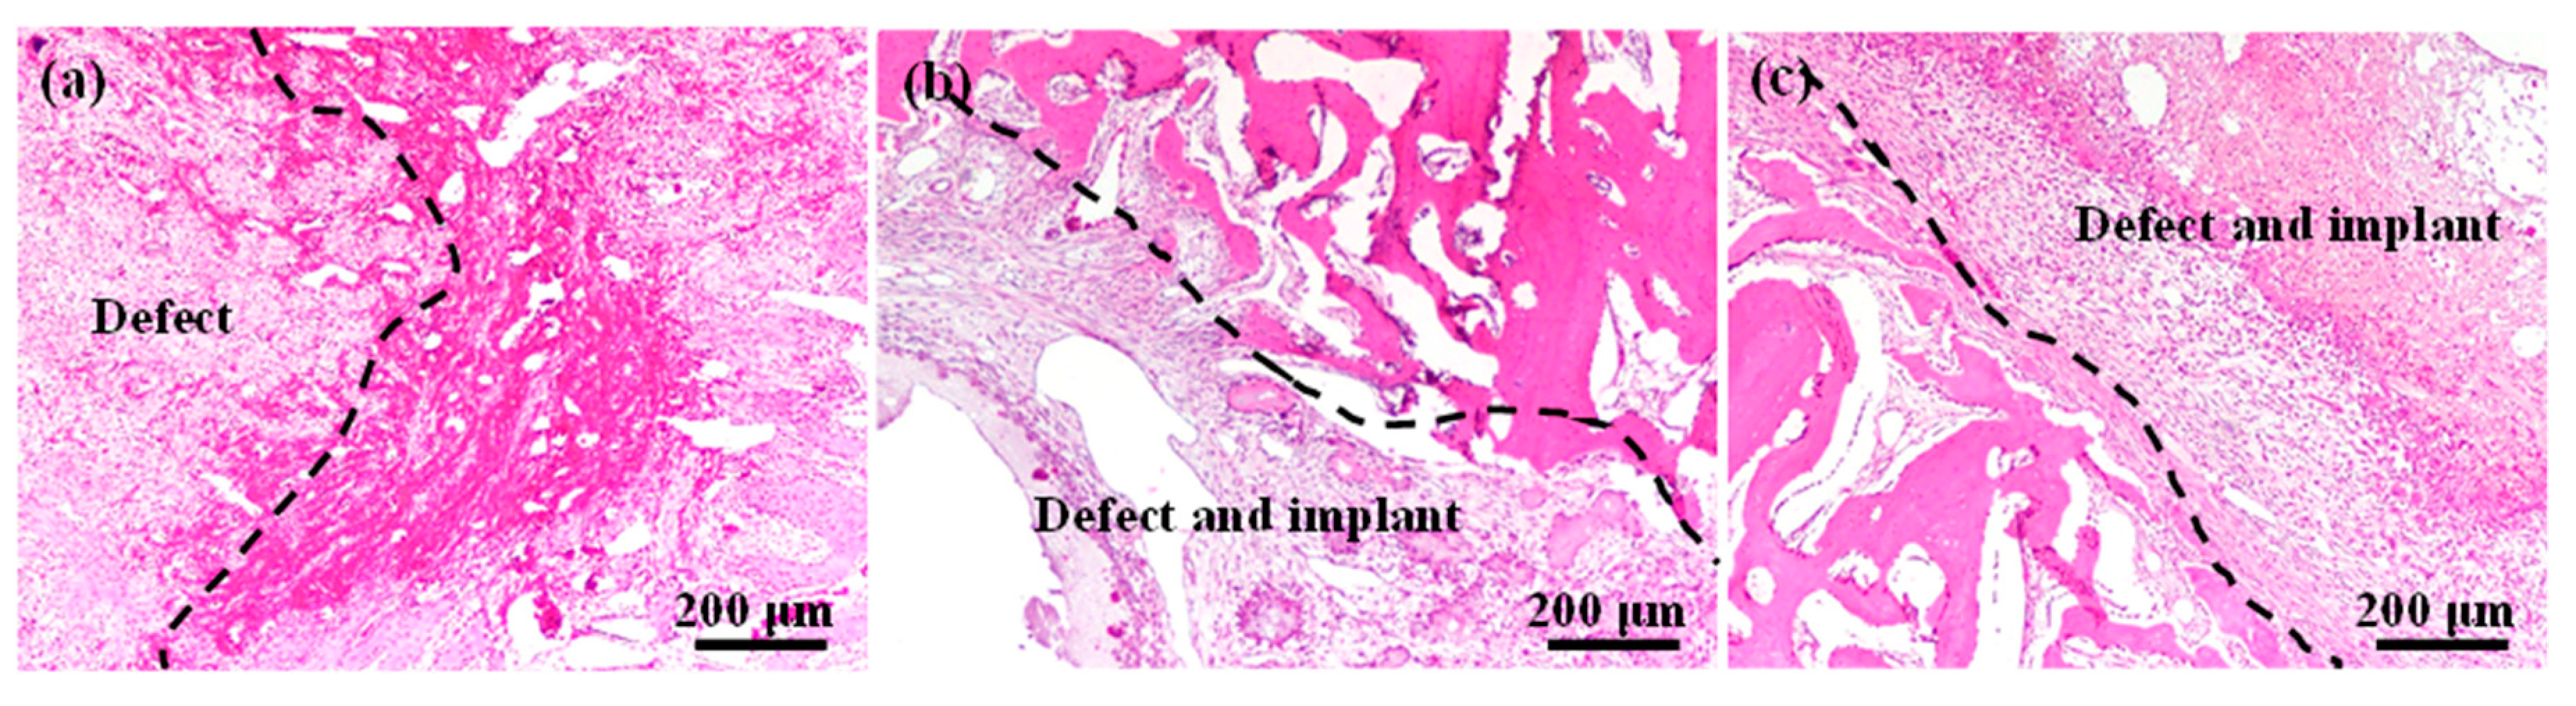

3.1. Bone Healing Features of the Implanted Materials

3.3. Bone Regeneration Characteristics of the Implanted Materials